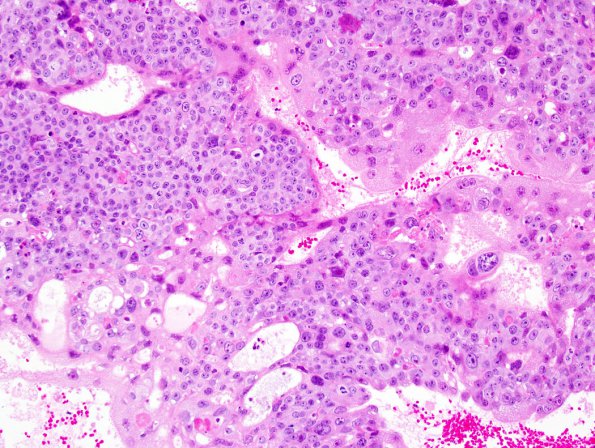

Intimate mixture of cytotrophoblasts and syncytiotrophoblasts which vary in density from site to site. (H&E)